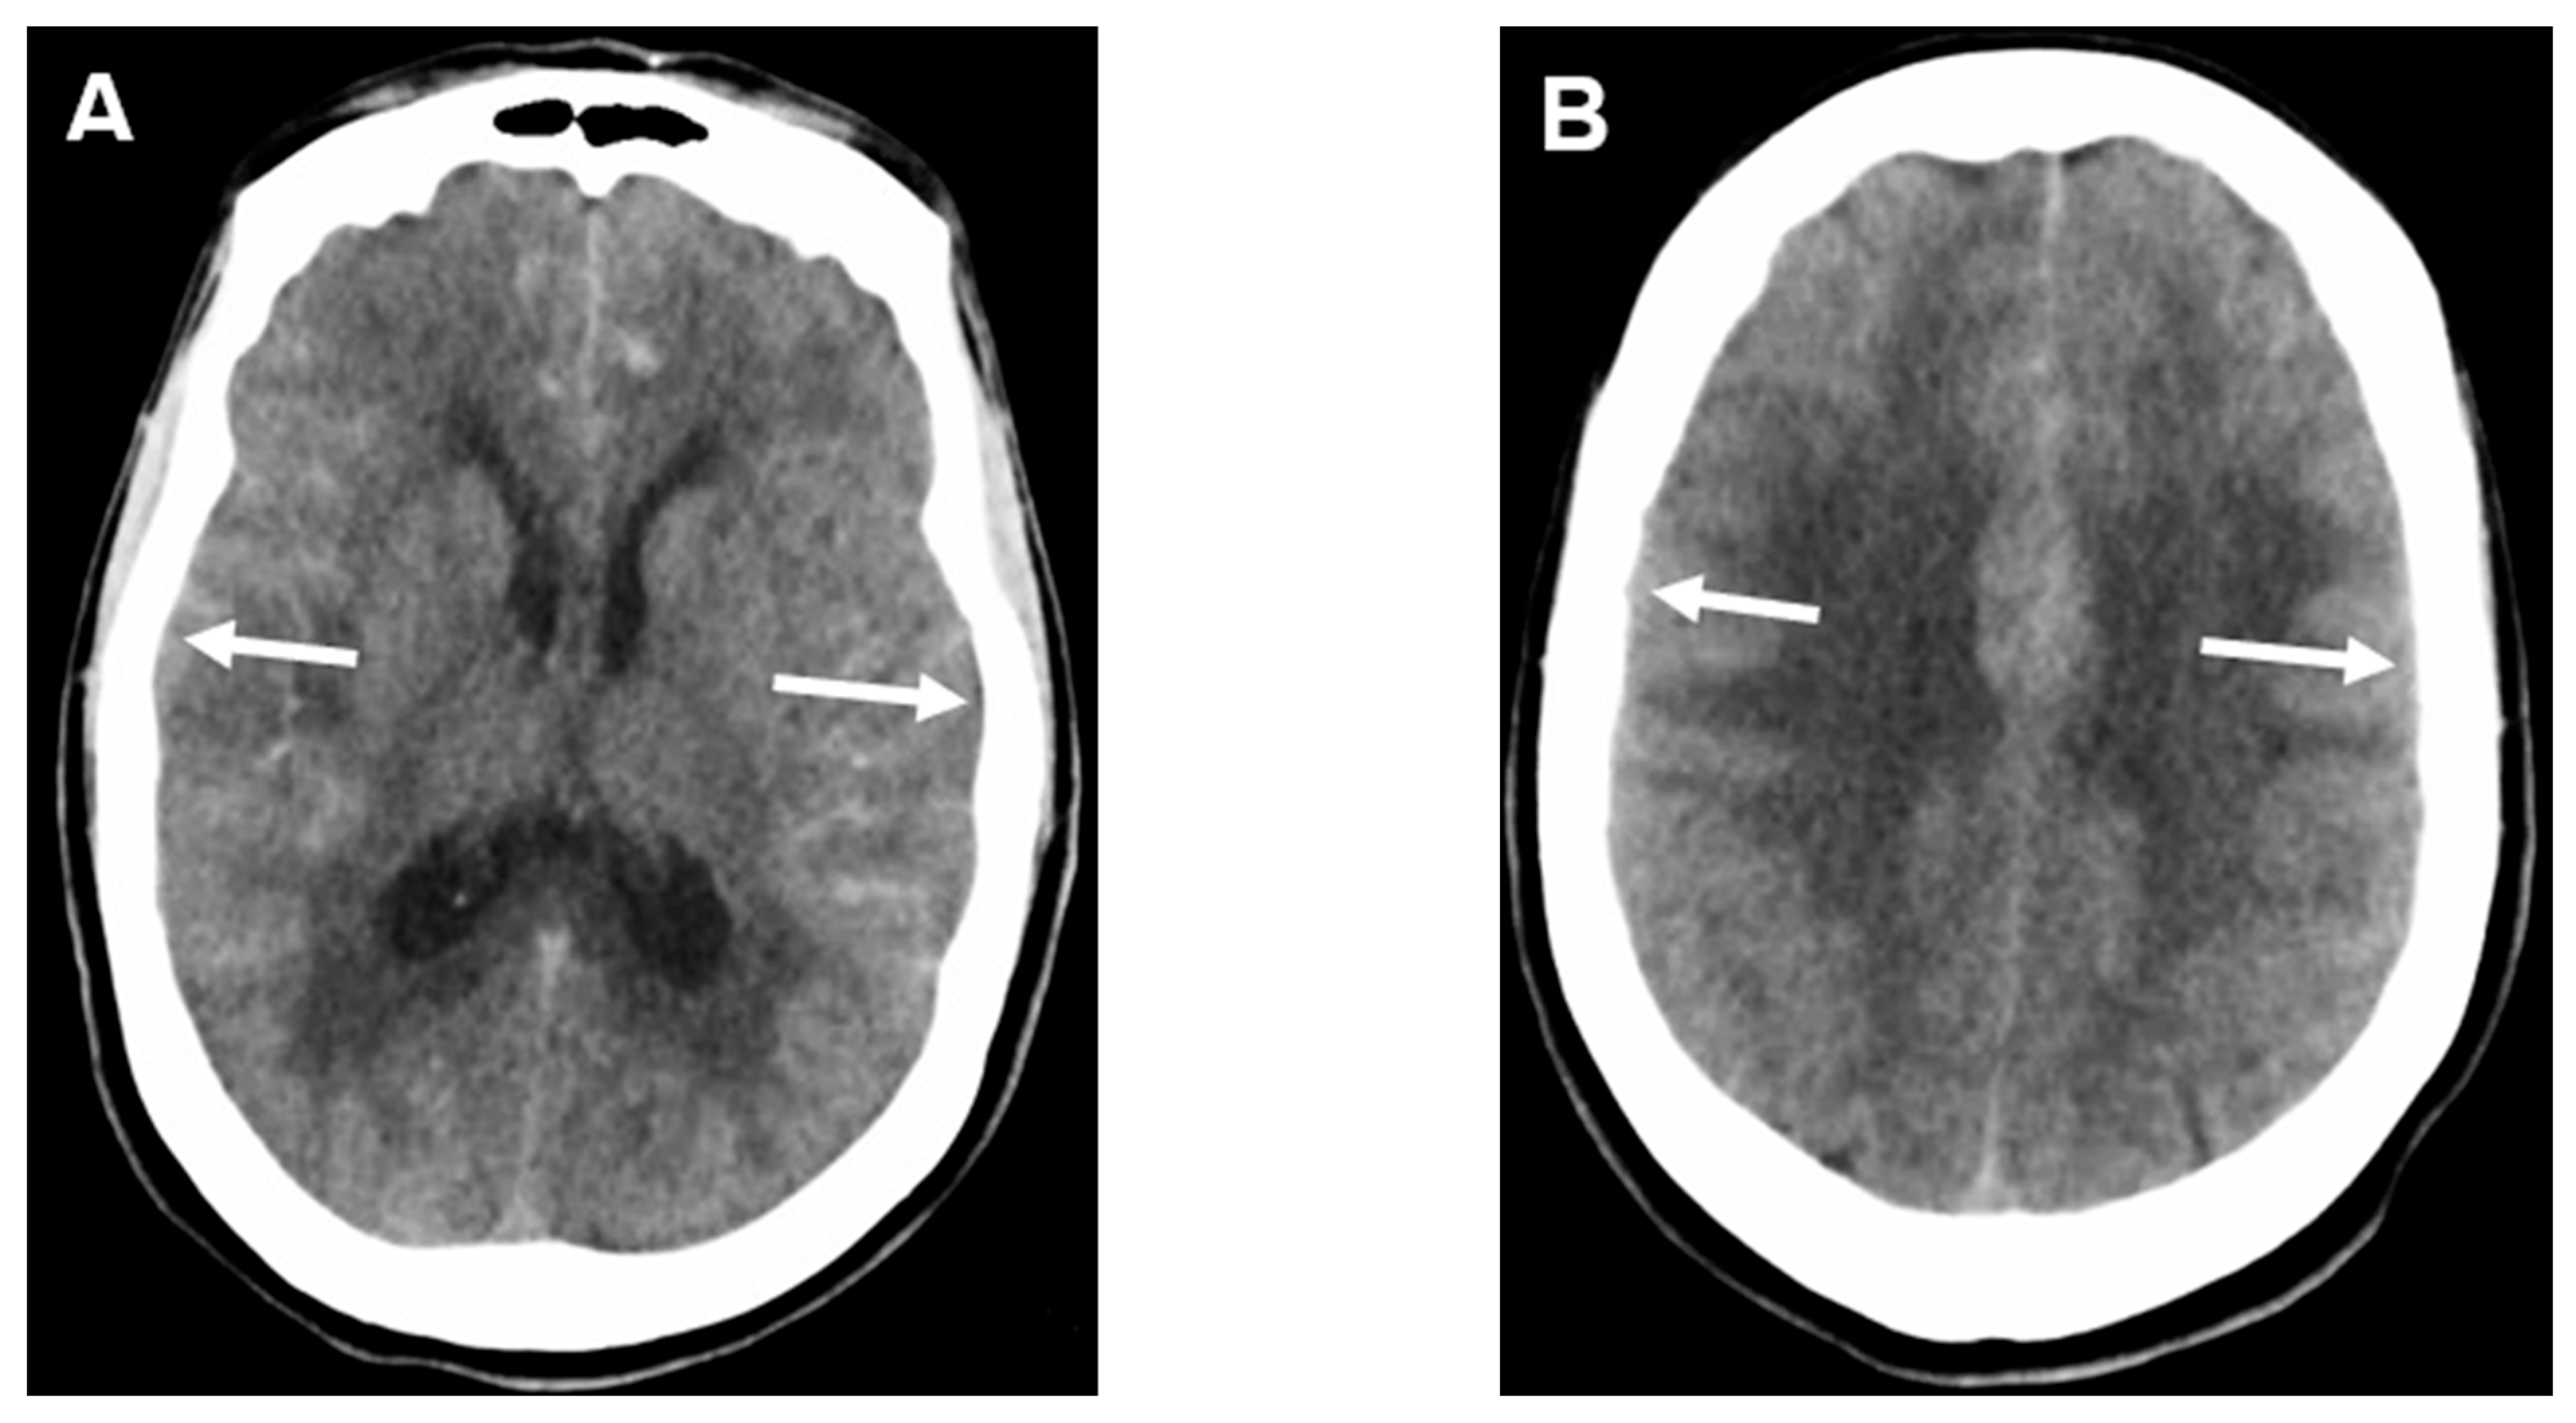

- Ahn, S.H.; Savarraj, J.P.; Pervez, M.; Jones, W.; Park, J.; Jeon, S.B.; Kwon, S.U.; Chang, T.R.; Lee, K.; Kim, D.H.; et al. The Subarachnoid Hemorrhage Early Brain Edema Score Predicts Delayed Cerebral Ischemia and Clinical Outcomes. Neurosurgery 2018, 83, 137–145. [Google Scholar] [CrossRef]